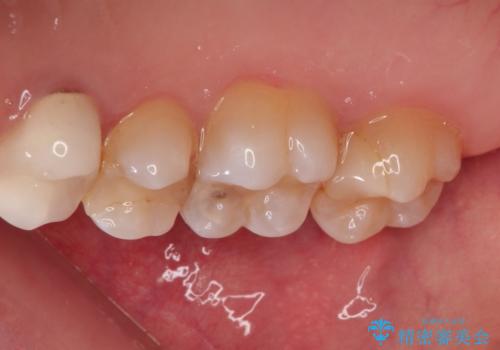

【VPT(歯髄温存療法)とセラミックインレー】深い虫歯でも神経を残したい

- 虫歯が大きく神経まで達していたので、VPT(歯髄温存療法)を行って細菌感染した部分の神経のみ取り除き、保存可能な神経は保存し被せ物はセラミックインレーで治療を行いました。

- 121,000円(VPT:44,000円 セラミックインレー:77,000円)費用は治療当時の料金となります